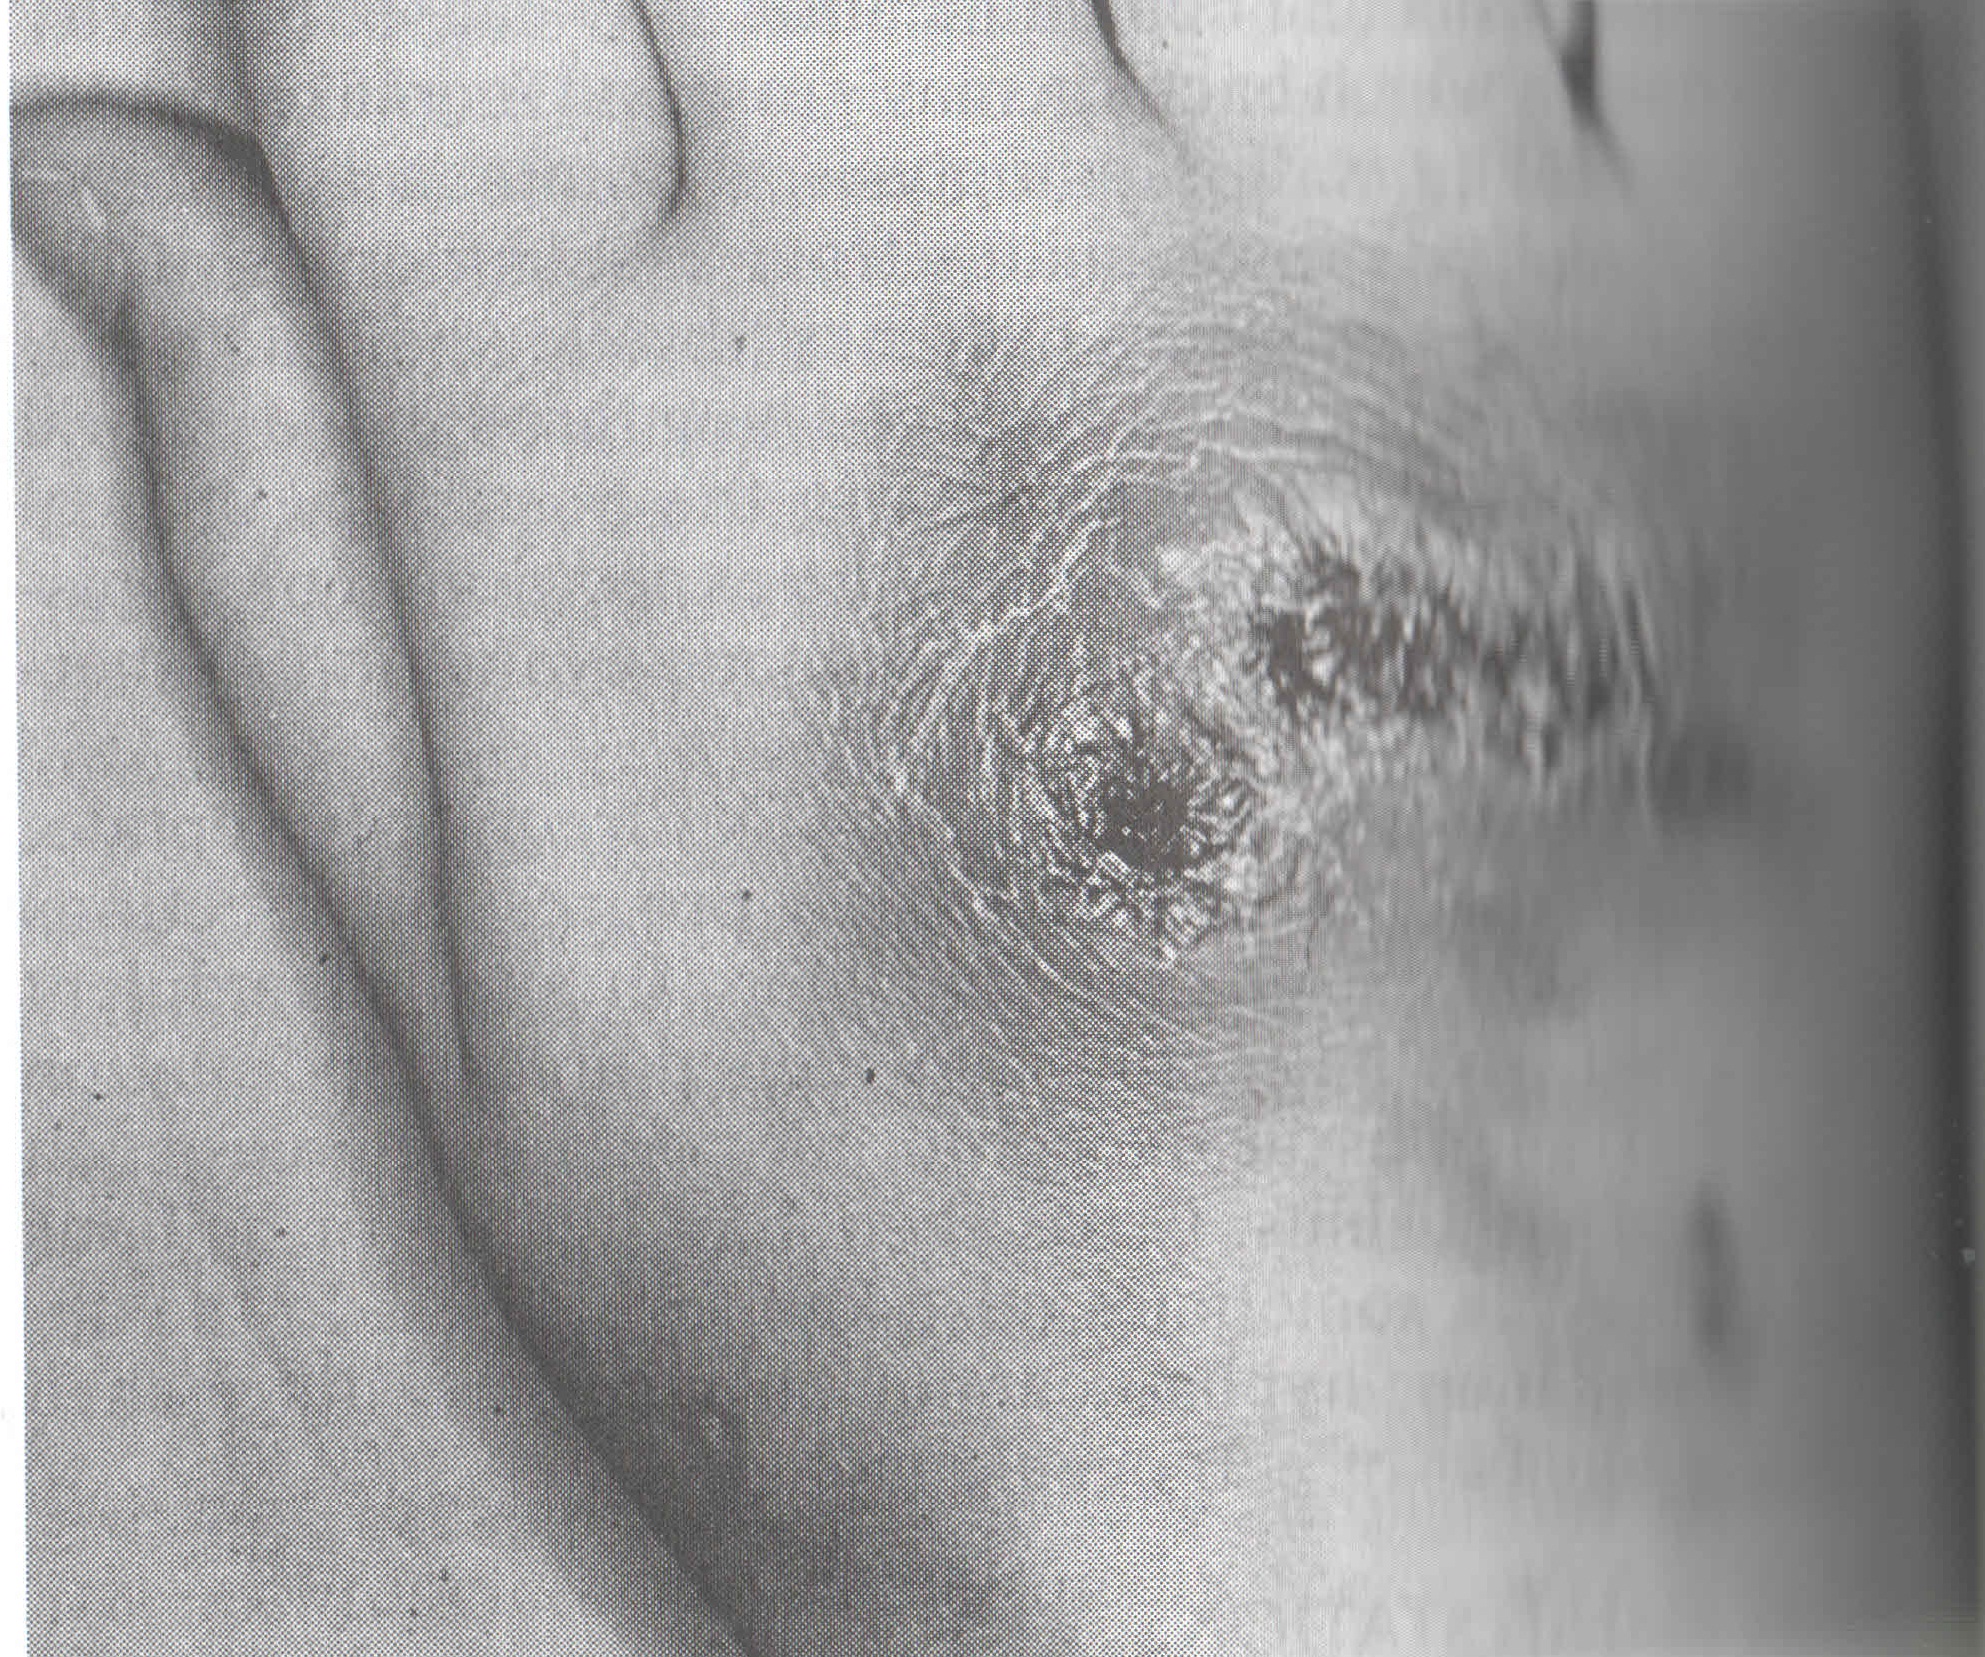

BLASTOMYCOSIS

Solunum yolu, cilt lezyonları verebilir ve yayılabilir. Patogonomonik semptomlar ve spesifik radyolojik bulgular vermez.

Kültürle kanıtlanmış olgularda, seroloji % 80 oranda uyum göstermiştir. Pozitif sonuçlar, gecikmeksizin tedaviyi gerektirir. Antikor titresi, hastalığın aktivitesiyle paraleldir